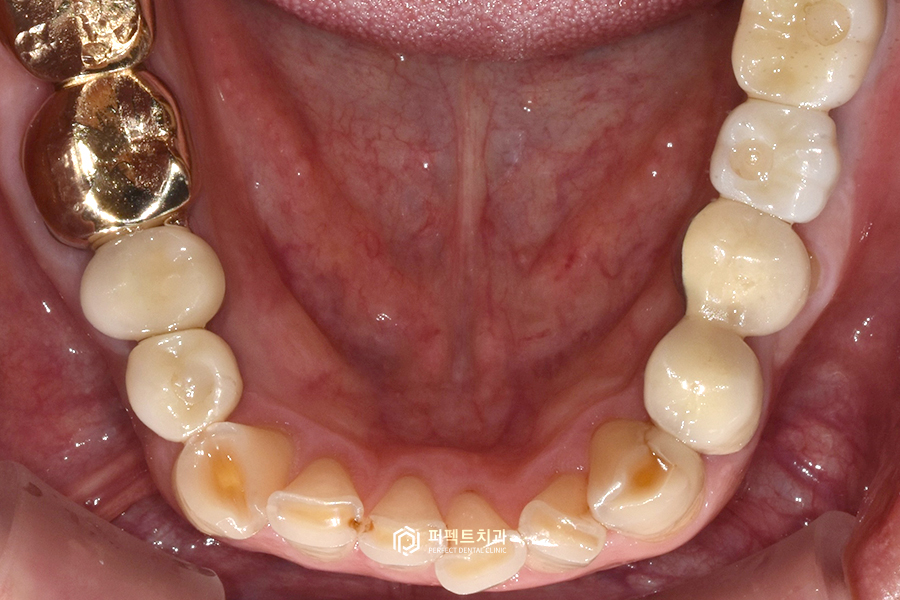

아랫니 같은 경우도 뿌리만 남은 부분들을 임플란트를 통해 수복을 했고, 자연치아는 쓸 수 있는 경우여서 치료를 하지 않고 그대로 사용하고 있는 경우입니다.

없는 치아들은 임플란트를 통해 수복을 했고 위, 아래 사랑니도 발치를 하였습니다. 그리고 마찬가지로 앞니 부분 옛날 보철들을 지르코니아 크라운으로 교체를 했습니다.

이렇게 어금니는 총 7개의 임플란트를 식립했고, 앞니 보철과 아랫니 부분도 꼭 해야하는 부분은 다시 재치료를 했습니다.